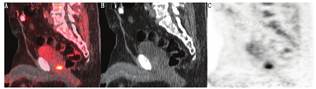

对于原位复发的前列腺癌,18F-fluciclovine PET/CT显像的灵敏度高,特异性低,PPV中等(图1)。一项纳入93例患者的研究结果显示18F-fluciclovine PET/CT的总体灵敏度、特异性、PPV和准确性分别为90.2%、40.0%、75.3%和73.6%[29],但该研究中的患者接受冷冻治疗或近距离放射治疗的比例相对高,治疗后炎性反应或前列腺增生可能导致显像出现假阳性,造成结果存在一定误差。针对根治性前列腺切除术后复发的前列腺癌患者的队列研究仍在进行中。一项纳入596例患者的大型多中心临床研究显示18F-fluciclovine PET/CT显像对前列腺癌局部复发的诊断效能与前述研究类似,灵敏度为88.1%,特异性为32.6%,PPV为71.8%[27]。因此,与原发性前列腺癌相同,对于原位复发的前列腺癌,18F-fluciclovine PET显像不能取代组织病理学诊断。

18F-fluciclovine PET/CT图像中,胰腺和肝脏可见明显生理性摄取,垂体、唾液腺、咽淋巴环、甲状腺、乳腺实质、食管、胃肠道、肾实质和肾上腺(单侧或双侧)可见不同程度的生理性摄取。肾肿物呈18F-fluciclovine高摄取则提示恶性。肾乳头状癌较正常肾实质摄取高,肾透明细胞癌与正常肾实质摄取相近[9]。膀胱壁呈轻至中度弥漫性生理性摄取;尿道周围组织呈轻至中度平行于尿道的片状放射性分布,可在矢状位图像上与前列腺床原位复发的局灶性摄取相鉴别(图1)。患者膀胱内尿液的放射性本底可能会干扰前列腺术区、前列腺和精囊内病灶的检出。对输尿管内的显像剂滞留不要误判为高摄取淋巴结。肾上腺可表现为单侧或者双侧轻至中度生理性摄取。注射侧的手臂或者锁骨下静脉有时会有放射性药物聚集,需要与高摄取淋巴结鉴别。